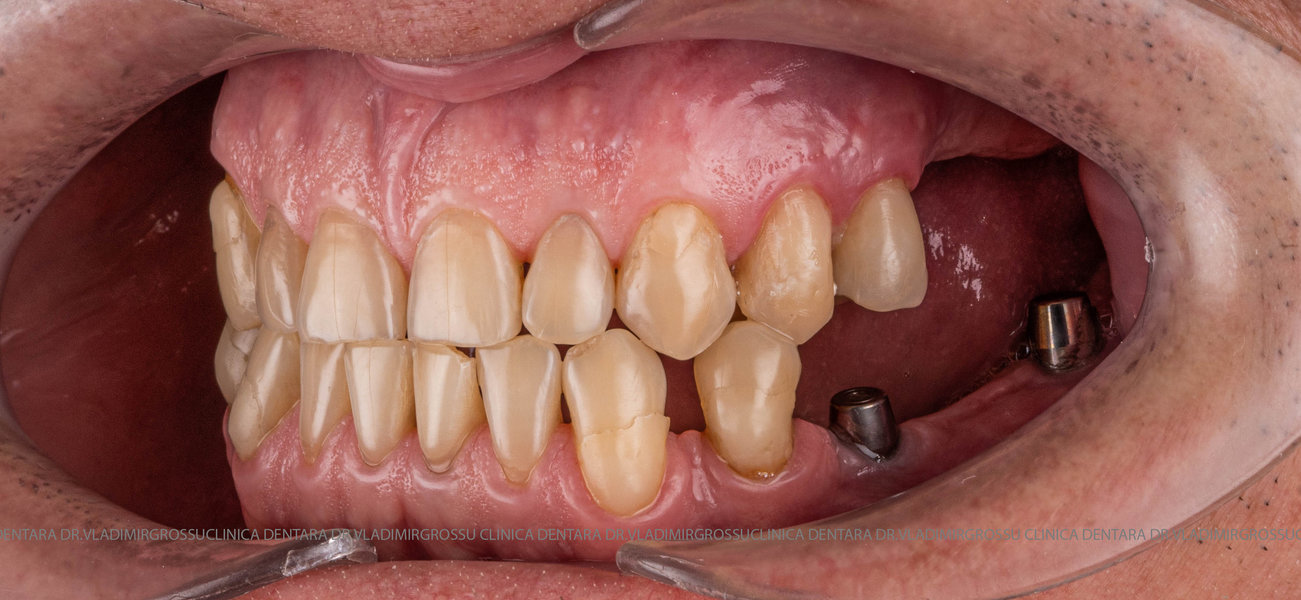

După inserarea unui implant dentar – o rădăcină artificială din titan sau zirconiu –, urmează etapa de protezare, adică atașarea unei structuri protetice (coroană, punte sau proteză) care înlocuiește dintele lipsă.

- Inserarea implanturilor dentare (chirurgie ghidată digital)

- Perioada de osteointegrare (3–6 luni)

- Persoane cu dinți lipsă parțial sau total

- Pacienți care nu se adaptează la protezele mobile